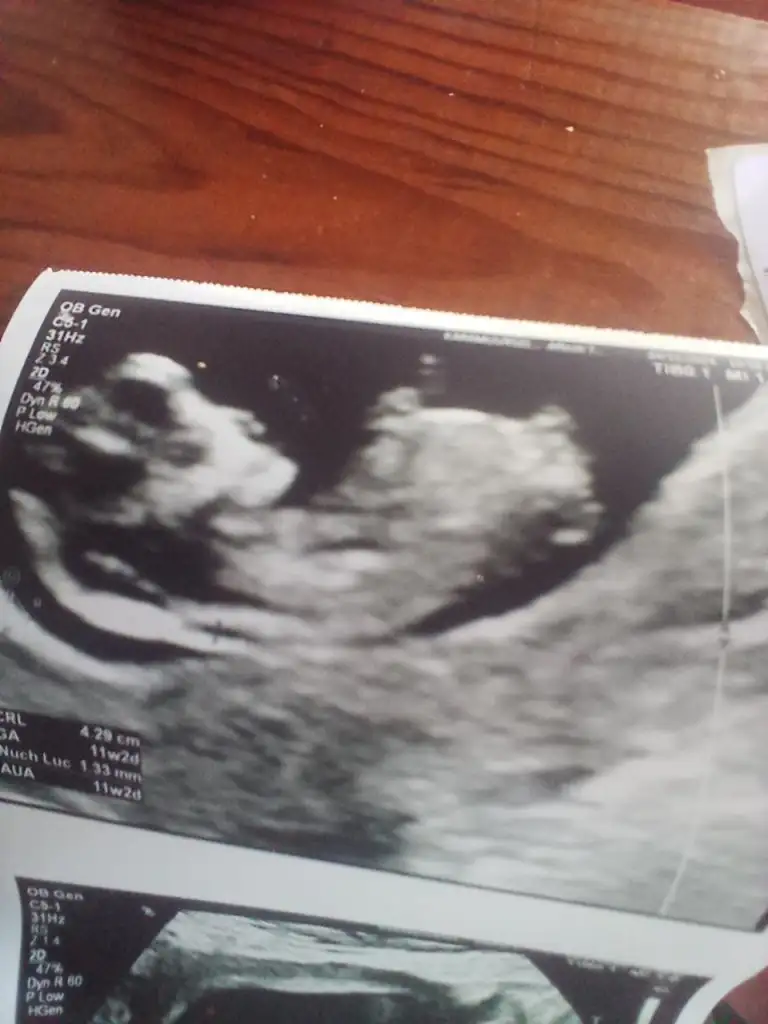

Banada bakabilirminiz 13 haftalık

• IMG_20241117_072114.webp

IMG_20241117_072114.webp

20,7 KB · Görüntüleme: 50